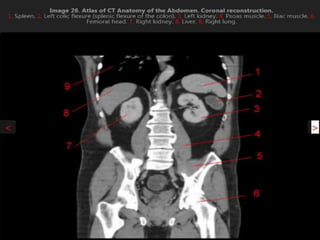

CT cross sectional anatomy.

CT – computedtomography. •Cross-sectional modality with capabilities for multiplanar reconstruction and dynamic imaging to assess vascularity •Tube rotates around the body and a circle of stationary detectors detects the penetrating x-rays forming an image.